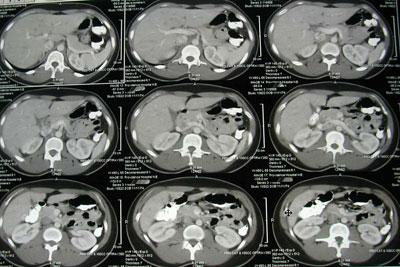

После приема потока ионизирующих лучей система датчиков передает информацию о состоянии внутренних органов на компьютер, с выводом снимков на дисплей диагностического аппарата. Сканирование организма больного выполняется послойно, через несколько миллиметров, в зависимости от выбранных параметров. Это позволяет получить с помощью компьютерных программ как детальное плоское изображение органов, участков опорно-двигательного аппарата, так и объемное изображение после компьютерной обработки снимков-срезов.

Полученное детальное графическое изображение всего организма больного можно увеличивать или уменьшать в масштабе, изучать в цифровом или бумажном виде. Такой метод обследования лечащие врачи назначают для подтверждения, а иногда и для уточнения поставленных ранее диагнозов, проведения промежуточных контролей курса лечения и диагностирования возможных патологий на ранних стадиях развития.

Данный способ обследования отличается от обычного рентгена тем, что в ходе сканирования пациента делается не один снимок, а целая последовательная цепь снимков в виде послойных срезов тела больного. Полученные снимки, после компьютерной обработки можно изучать как на мониторе аппарата, так и на бумажном носителе. Снимки представляют собой плоские и объемные изображения внутренних органов.